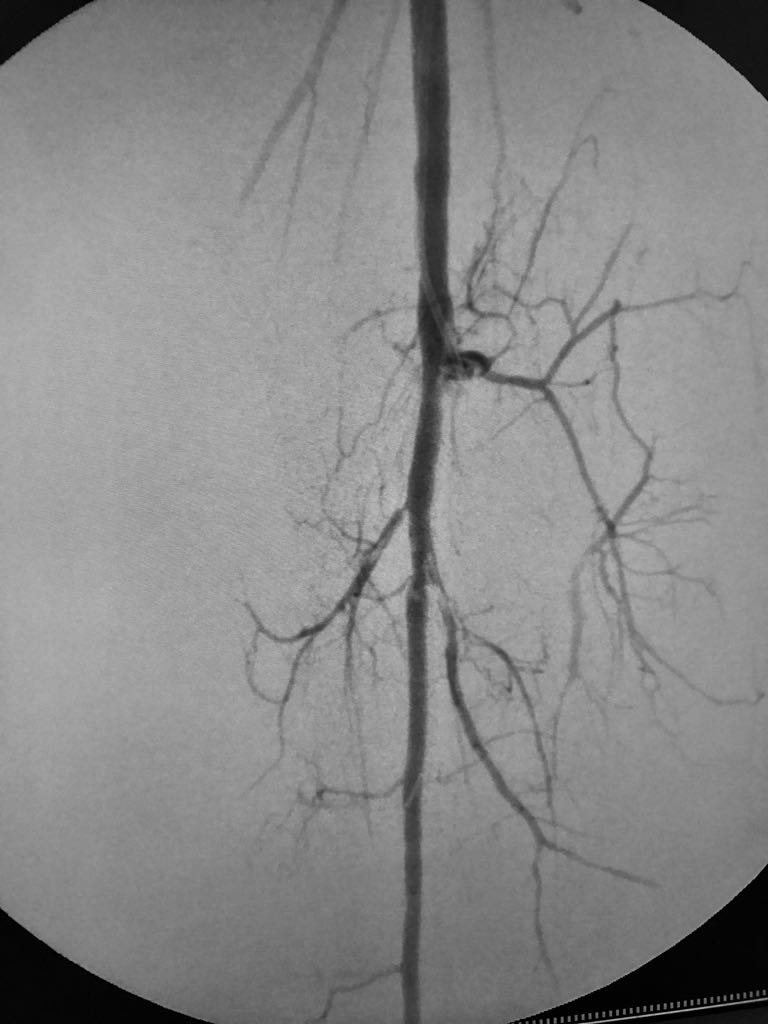

Somos una empresa enfocada en la atención en salud humana por medio del uso imágenes para ver diagnosticos y tratamientos de las diversas patologías con el uso de técnicas mínimamente invasivas en el territorio colombiano en el sector público y privado en búsqueda de una atención oportuna y de calidad a cada uno de nuestros pacientes.